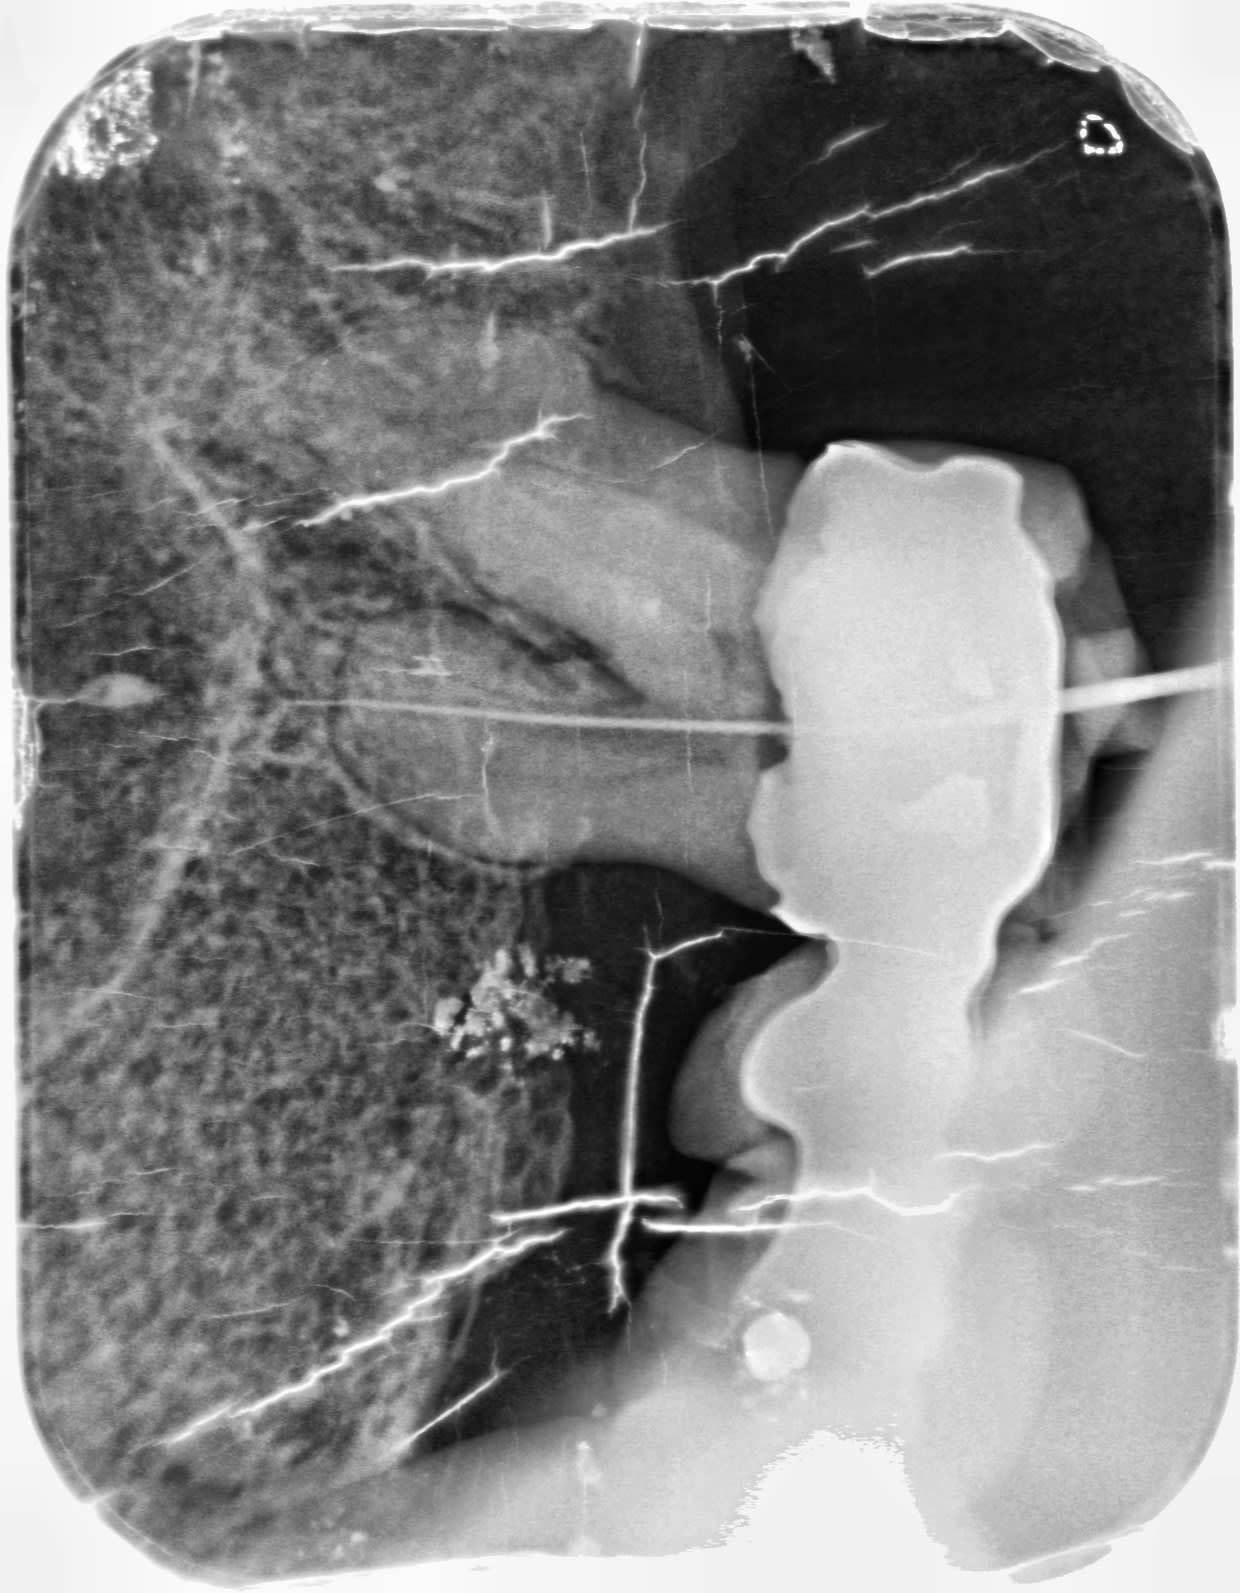

Je crois plutôt que tu as surtout travaillé dans la carie... ;)

Cette dent est fichue, tout est carié sous la couronne, tout comme tes films :)))

Oui le bridge n’était vraiment plus étanche,il faut le virer voir si la dent est conservable ou pas parce que l’image donne l’impression d’une atteinte du plancher.

ça ne m'étonnerait pas que tes entrées ''évidentes'' soient des perfs

Cest ce qu'a écrit Hokusai. La carie qui a rompu le plancher pulpaire et faux canaux.

oui mais vous savez quand on fait une perforation, on le sent inconsciemment, différence de resistance dans la rotation, on ressort sa lime pleine de sang, on a un écoulement sanguin qui persiste,hors là il ne me semble pas que cela ait été le cas